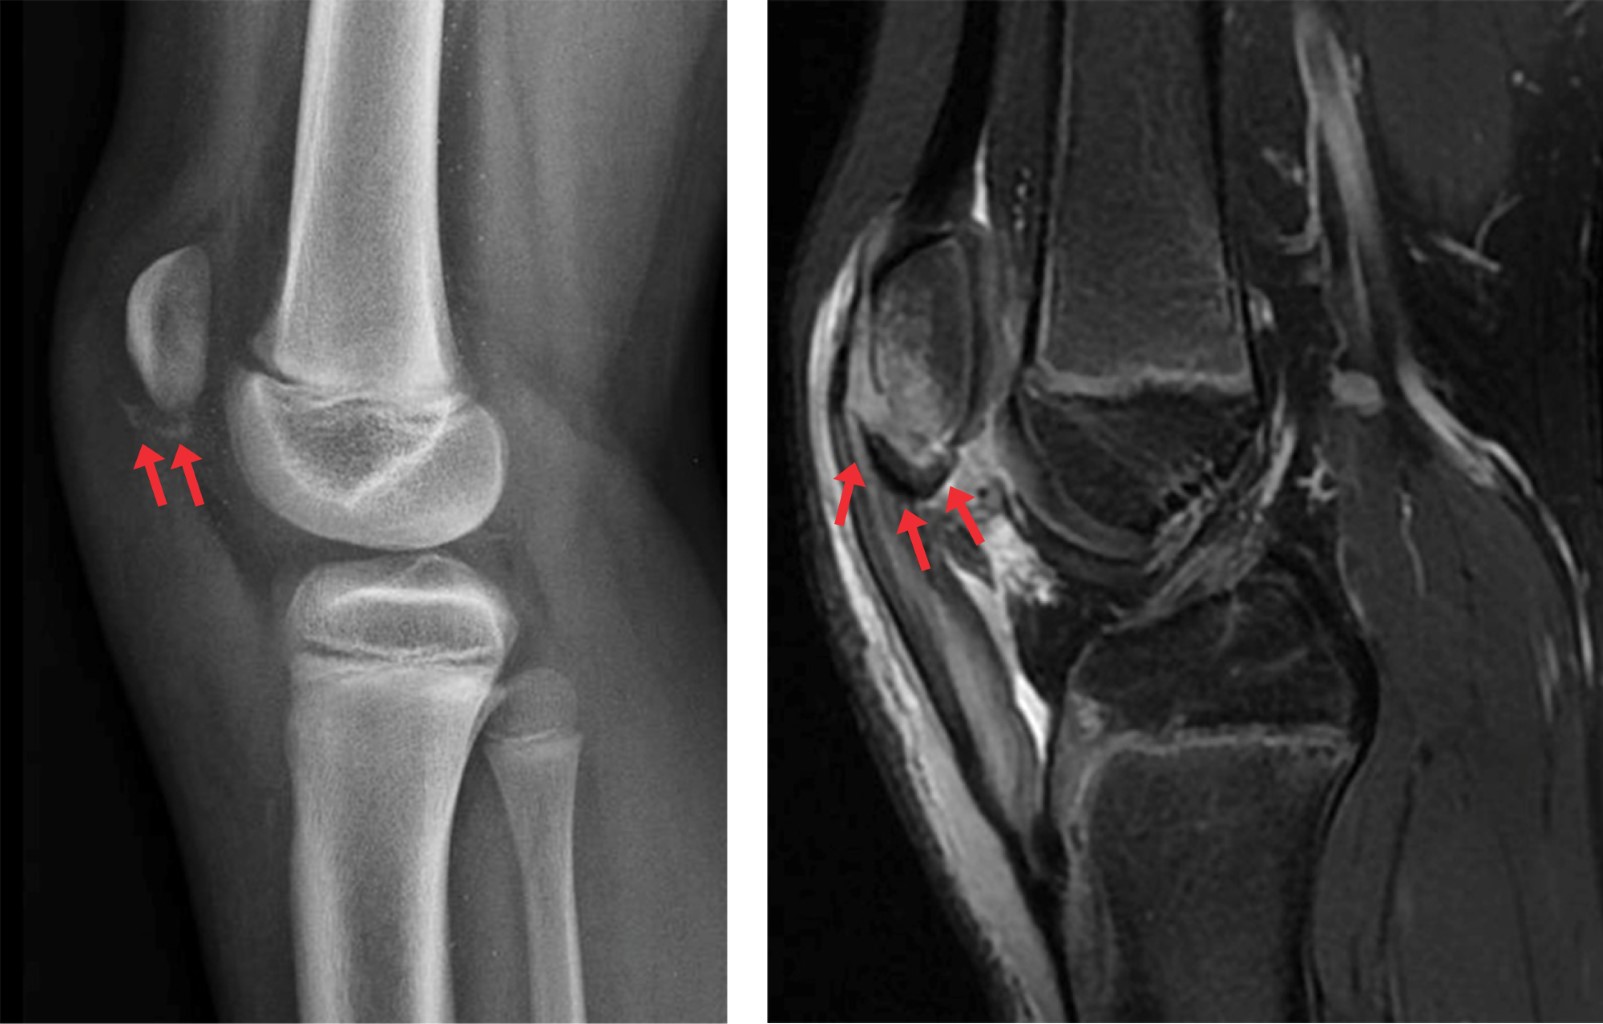

Sleeve fractures are rare injuries seen almost exclusively in skeletally immature patients characterized by separation of a "sleeve" of cartilage or periosteum with or without an osseous fragment. Patients with sleeve fractures present with a hemarthrosis, the inability to extend the knee, and either patella alta (inferior sleeve) or patella baja (superior sleeve). The diagnosis of these injuries could be challenging. Large osseous fragments are obvious on plain radiographs, but in some cases, they are easily missed, because only a minimal portion of bone is avulsed, and the fragment is largely composed of un-ossified peripheral cartilage. MRI can confirm the injury pattern and can be helpful to evaluate the size of the sleeve. Failure to diagnose these injuries can result in patellar instability, extensor lag, and anterior knee pain.52

Sleeve fractures can be classified by the location of the avulsion into proximal patellar pole, distal patellar pole (most common), and tibial metaphysis.53 Most fractures are displaced and require treatment with open reduction and internal fixation. Non-operative management can be considered in non-displaced fractures (2 mm or less), if active knee extension is intact. Sousa et al.54 evaluated five patients with distal pole sleeve fracture treated nonoperatively. Final radiographic evaluation revealed fracture healing and all five patients had full terminal knee extension and symmetric range of motion. Mean IKDC score was 96.4 (range: 82-100) mean Tegner's activity score was 60 (range: 5-8), and mean Kujala's score was 89.7 (range: 63-100) at final follow-up.

Non-displaced inferior pole fractures can be easily confused with Sinding-Larsen-Johansson syndrome (SLJS) (Figure 3).55 Displaced fractures can be stabilized using transosseous sutures, suture anchors, small screws with suture supplementation, or tension band wiring.15 Torn medial/lateral retinaculum and/or quadriceps/patellar tendon are commonly associated findings and should be repaired if present. Immobilization in a brace for three to four weeks is required post operatively. Data regarding clinical outcomes after surgical treatment of sleeve fractures is limited, and mostly limited to case reports and very small case series. Perkins et al,56 in the largest case series in the literature, evaluated 20 patients (17 males, mean age of 11.7 years), treated with transosseous repair. All patients had a healed patellar sleeve fracture and intact extensor function at final follow-up. Final mean knee ROM among the 18 patients with minimum 3-month follow-up was 132 degrees. Thirteen patients (72%) achieved full ROM (≥ 130 degrees) and five patients (28%) achieved less than 130 degrees knee flexion. No patients experienced construct failure or extensor lag.

Sleeve fractures can lead to complications if not treated appropriately and in a timely fashion. Complications of missed or untreated patellar sleeve fractures include malunion, patella alta, anterior knee pain, and quadriceps atrophy. These can all result in severe limitations in daily activity.57